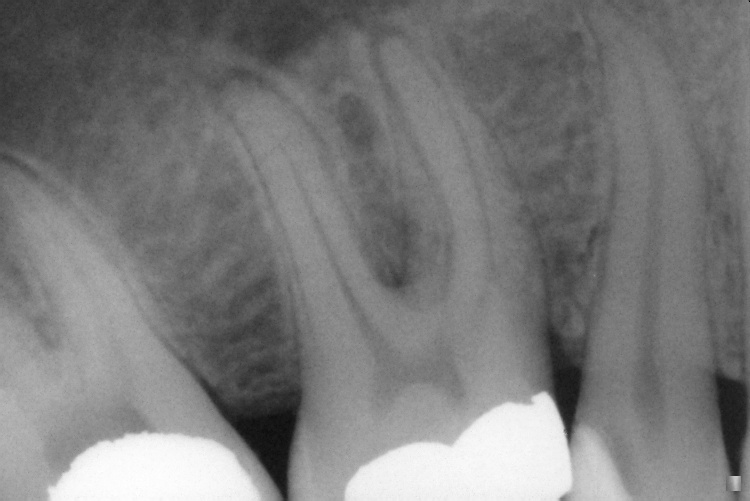

IO000001.jpg

2020-07-28 13:39 87K